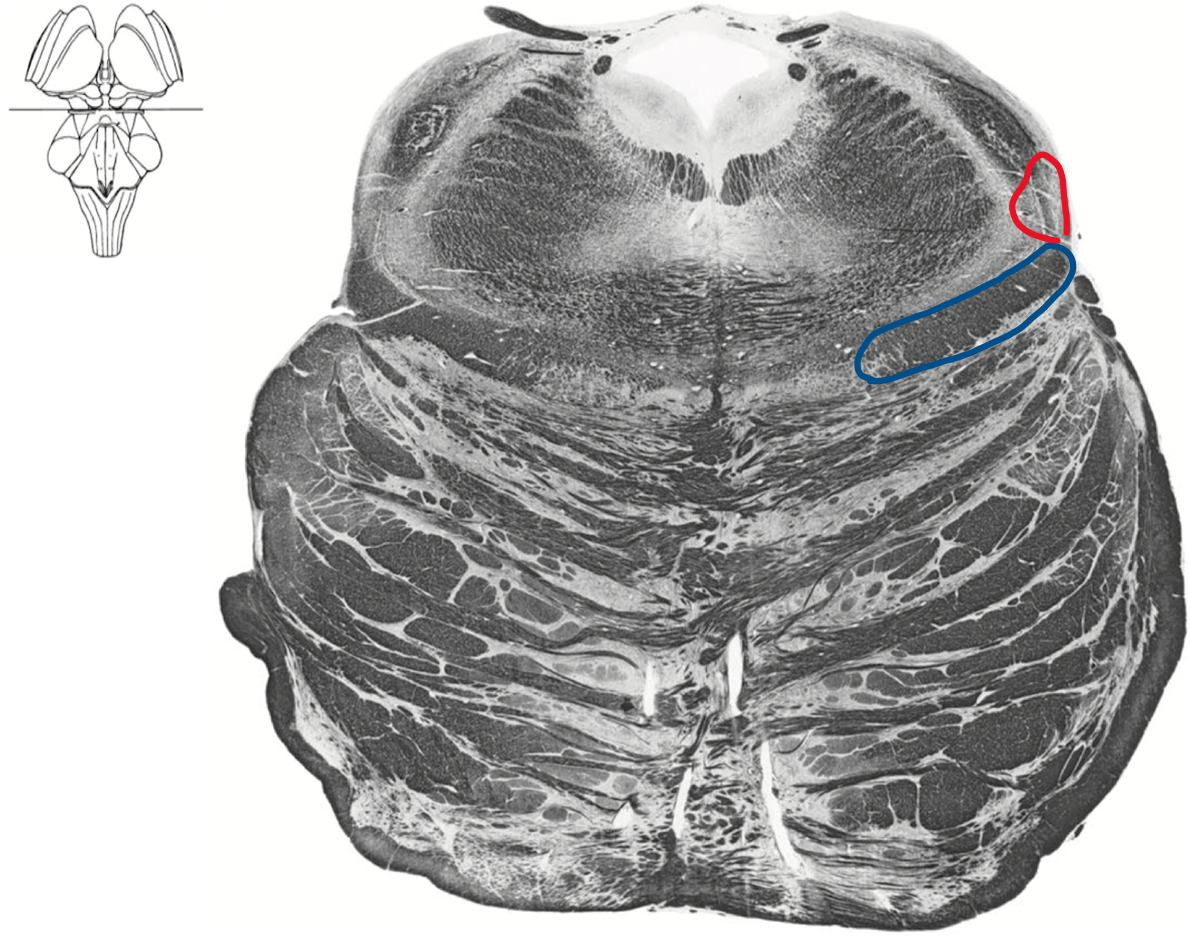

Rostral pons

Boomerang

Blue Ventral medial lemniscus (DCML)

Red ALS spinothalamic tract